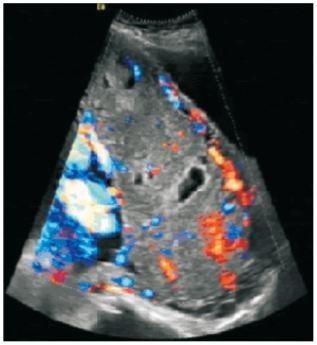

彩超检查示:胎盘附着左、右壁及侧壁、下缘覆盖宫颈内口,前壁部分与子宫肌壁分界不清,肌层薄,局部外凸,胎盘内见数个液性暗区,较大范围者约59mm×30mm,血流信号丰富,提示中央型前置胎盘,胎盘植入,见图1。

图1胎盘彩超